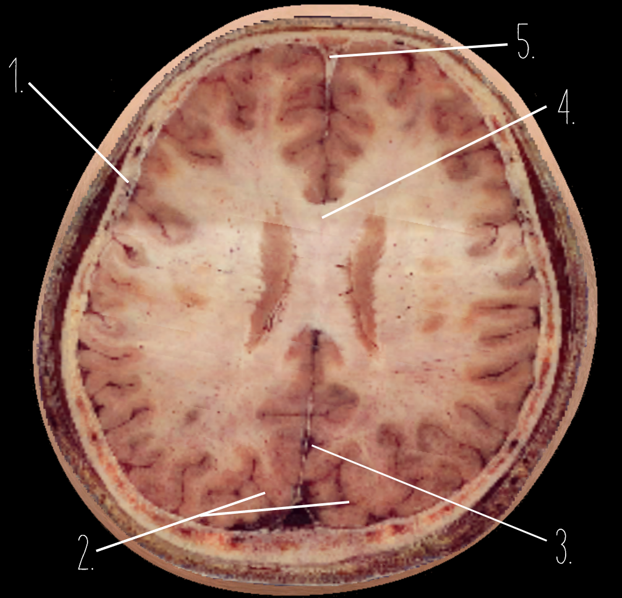

1?

Anterior Horn of the Lateral Ventricle

2?

Putamen

3?

Thalamus

4?

Internal Occipital Protuberance

5?

Cerebellar Vermis

6?

Third Ventricle